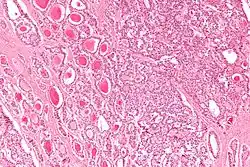

Micrograph of a strumal carcinoid. H&E stain.

The strumal carcinoid is a type of monodermal teratoma with histomorphologic features of (1) the thyroid gland and (2) a neuroendocrine tumour (carcinoid).[1][2]